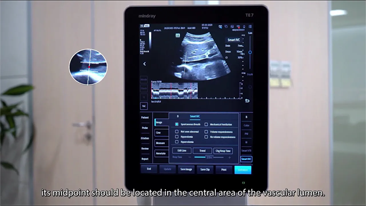

Mindray offers the most comprehensive portfolio of Point of Care ultrasound solutions that are easy to use, elevate your practice, and empower you to provide an even higher standard of care in a timely manner. From entry-level, touch-enabled systems to sophisticated, laptop or cart-based designs, our Point of Care ultrasound machines are an excellent choice to meet the demands of fast-paced environments such as Emergency Medicine, Critical Care, Anesthesia, and others.

MindrayŌĆÖs Point of Care ultrasound machines provide leading-edge technology and everyday applications that meet the diverse demands of your departments and the evolving needs of your patient population. Our innovative, accessible Point of Care ultrasound solutions offer sophisticated tools and technologies that empower you to streamline workflow, minimize the risk of infection, and provide the highest quality of care now and in the future. Experience peace of mind and see something better with Mindray Ultrasound.